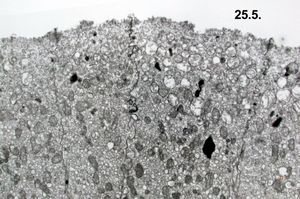

normal mucosa - stomach